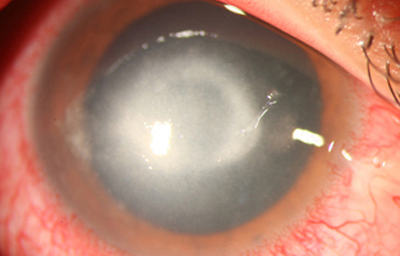

Superficie corneal irregular y grisácea, (Fig. 1, 2) con opácidades granulares en parche y formación de líneas epiteliales elevadas de aspecto granular (Fig. 3), que pueden arborizar dando imágenes de pseudodendritas. Opacidades superficiales satélites. (Figura 4) Inyección ciliar. Ulceración epitelial variante. (Figura 5).

Fig. 4 Focos satélites. Síntomas de meses evolución.